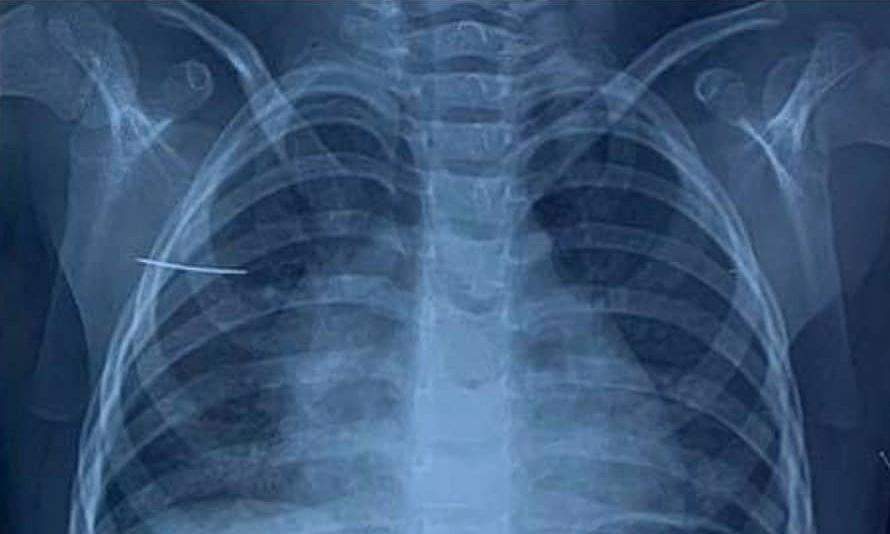

Kết quả chụp X-quang và cắt vi tính lồng ngực phát hiện dị vật hình kim khâu nằm tại mặt trước xương bả vai bé.

Bác sĩ Nguyễn Minh Khôi, khoa Ngoại tổng hợp, cho biết khi phẫu thuật nội soi vào giữa cơ dưới vai và cơ thang, các bác sĩ phát hiện nằm lẫn trong các sợi cơ là chiếc kim khâu dài gần 4 cm, đầu nhọn. Sau một giờ nội soi, chiếc kim đã được lấy ra hoàn toàn, không đứt gãy.